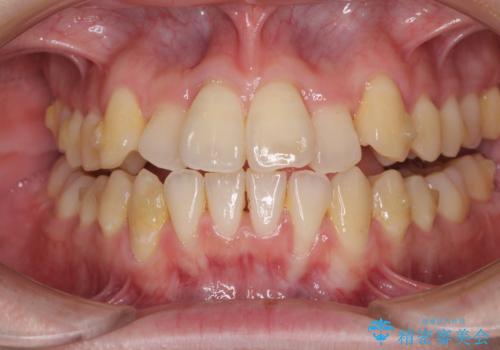

前歯のクロスバイト インビザラインによる矯正治療

- 上下のクロスバイトと前歯のデコボコを気にして来院された患者様です。

インビザラインを用い、IPR(歯と歯の間を削る)と歯列全体を拡大させることで、歯並びを整えていくこととしました。

奥に位置していた上の前歯が下の前歯を乗り越える際、奥歯でものを咬むことができず、辛い時期が続きました。